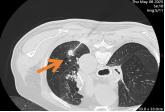

时间来到2025年3月,随访CT再次发现张大叔左下肺有新发小结节,穿刺病理仍为“Ia期肺腺癌”,无基因突变。此时的他早已褪去最初的惶恐,每次来院都自带保温杯,笑着和护士打招呼,说起复查流程比年轻患者还熟络。全院MDT再次启动,呼吸科、介入科、病理科专家反复研判后认为,鉴于患者有两次肺癌病史且年龄增长,微创的微波消融治疗比手术更适合。今年5月,介入科团队为他完成了微波消融术,整个过程仅耗时半小时。6月复查时,消融病灶已完全坏死,无复发迹象。

图3 第三次诊断肺癌,行微波消融治疗